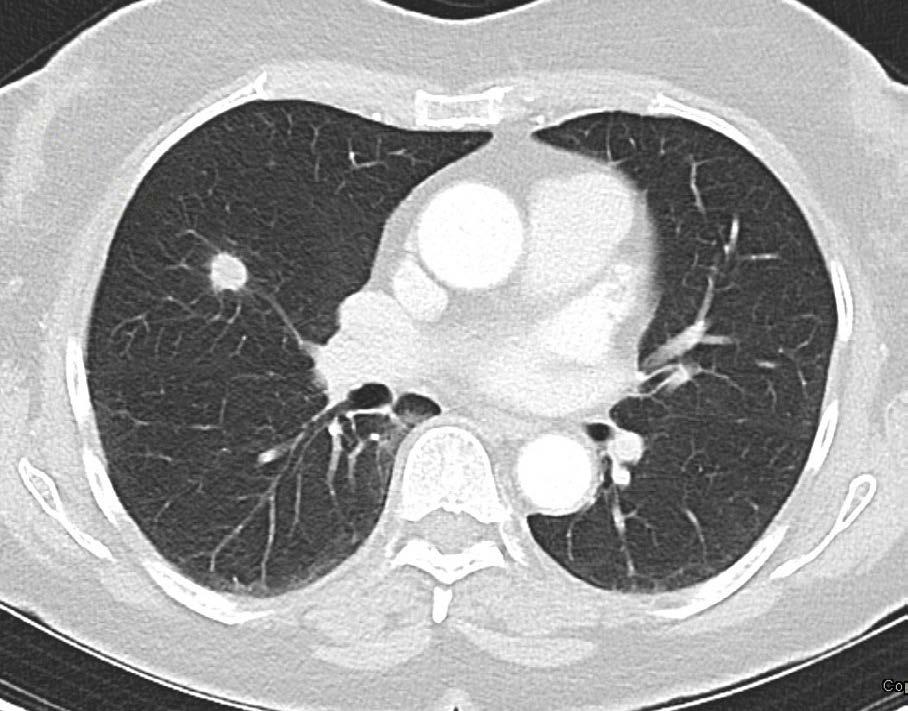

Mynd 6-1 Lítið lungnakrabbamein í hægra lunga (ör) sem fannst við skimun með tölvusneiðmyndum.

Með tilkomu tölvusneiðmyndatækni (TS) varð unnt að finna mun smærri hnúta í lungum en áður var mögulegt með hefðbundnum röntgenmyndum (mynd 6-1). Á síðustu áratugum hefur verið efnt til stórra framvirkra samstarfsverkefna, bæði í Bandaríkjunum og Evrópu. Fyrstu rannsóknir á skimun með TS voru gerðar í Japan og fyrsta alþjóðlega rannsóknin benti til þess að unnt væri að finna um